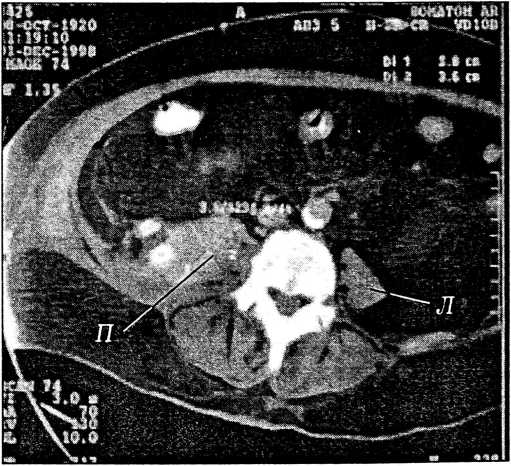

Микроскопически: в материале из верхних конечностей выраженное гнойно-некротическое воспаление (нейтрофильная инфильтрация, детрит среди гемолизированных эритроцитов) с распространением воспалительного процесса на мышечную ткань. Атрофия мышечных волокон с замещением их фиброзной тканью (давность наиболее «старых» изменений — около 4 нед), выраженные дистрофические изменения мышечных волокон с миомаляцией, миолизом и очаговым некрозом; начальные признаки организации в виде развития молодой фиброзной ткани, скудной клеточной реакции в виде очаговой лимфоидной и диффузной гистиоцитарно-плазмоцитарно-макрофагальной инфильтрации. В участках некроза мышечной ткани имеются мелкие очаги гнойного воспаления. На этом фоне определяются обширные кровоизлияния (по типу гематом) различной давности: свежие межмышечные, внутрифасциальные и перифокальные скопления эритроцитов; гематомы с выраженным гемолизом эритроцитов, вторичной коликвацией с образованием полостей, содержащих гемосидерофаги, с начальными признаками организации в виде новообразования капиллярных почек и прорастания фибробластов (рис. 6).

Рис. 6. Пациентка М. Микропрепарат фрагмента двуглавой мышцы правого плеча: атрофия и замещение поперечно-полосатой мышцы волокнистой соединительной и жировой тканью (в левой части микрофотографии); некроз мышечной ткани (в правой части микрофотографии). Окраска гематоксилином и эозином. Ув. 400.